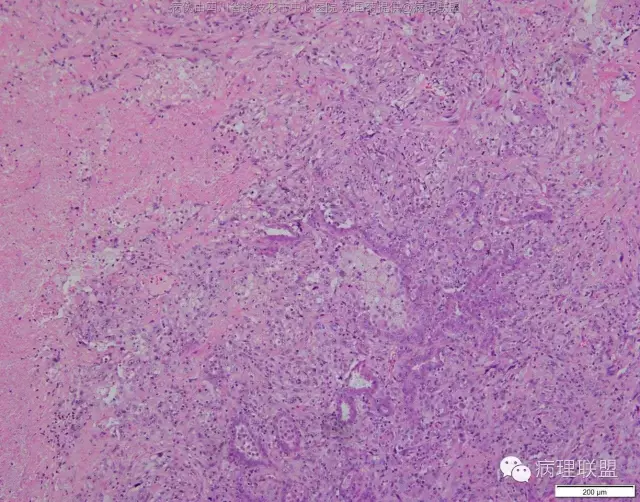

M/47 肺部占位,大小2*1*0.6cm(病例由四川攀枝花市中心医院 沈国菊提供,致谢!)

@张丽 免疫组化腺癌,鳞癌,神经内分泌,恶黑标记均为阴性,只有广谱CK跟Vimentin阳性,准备发大细胞癌

@沈国菊 肺大细胞癌的签发有时是个排他性诊断,我的体会:大细胞的标准:按淋巴细胞直径3倍来算,需要大于这个值,不能等于(从图给出,符合)。神经内分泌的标记(CD56 SYN CgA)完全阴性的可能性不是没有,建议重做试试;细胞的异型性大(符合);Ki67的指数高,应该非常高(您这里没有给出)。这仅仅是我个人体会,我说的不一定正确。

感谢您的精彩病例,采图非常漂亮,并且有标尺(特别赞)。魏老师,Ki-67阳性大于90%,送检7组淋巴结6/7见肿瘤转移。